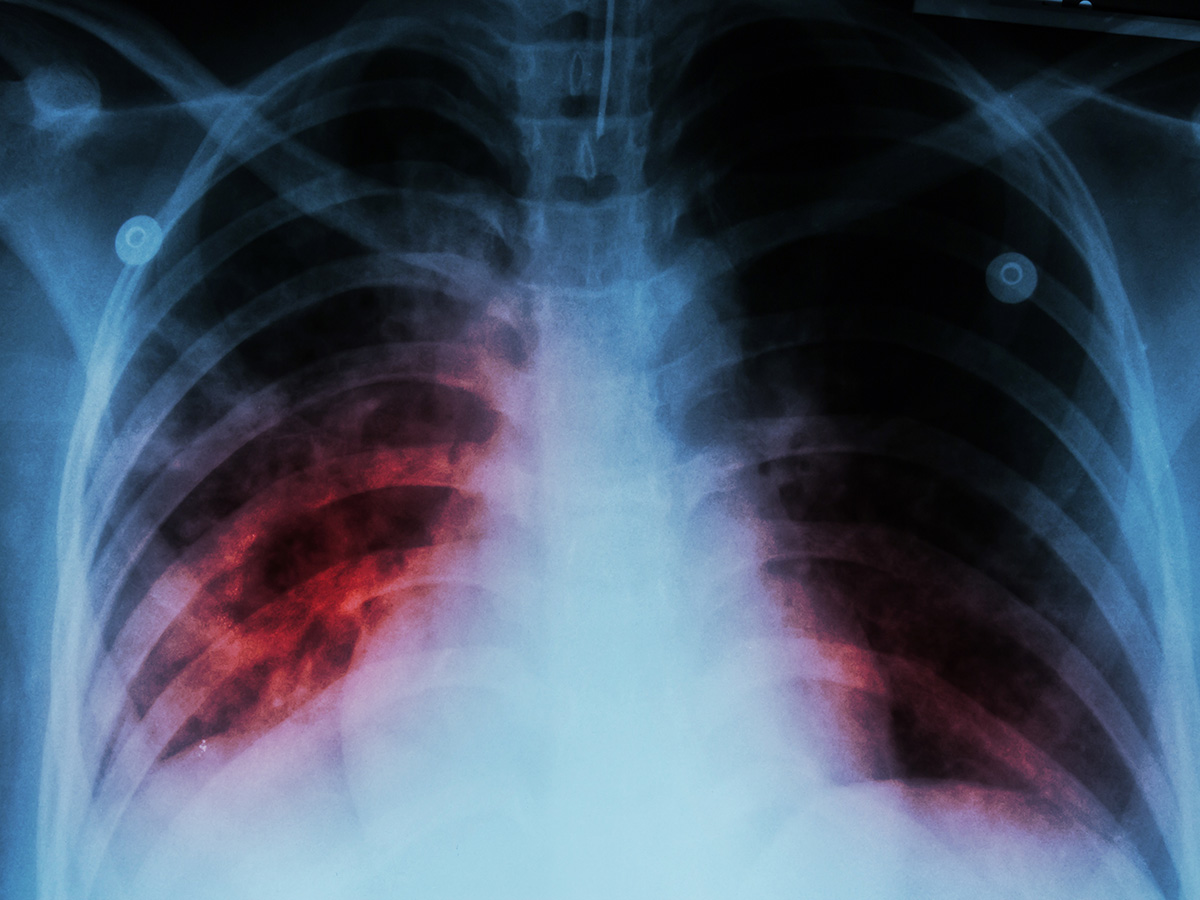

Millions of Americans who acquired COVID-19 experience persistent respiratory symptoms—including breathlessness, coughing, and chest pain—lasting over three months, known as long COVID. A study led by researchers at UAB and the University of North Carolina at Chapel Hill revealed a previously underappreciated mechanism by which SARS-CoV-2 infection contributes to long-term lung damage. The study, published in Nature Microbiology, demonstrates that SARS-CoV-2 uniquely induces the formation of foam cells—lipid-laden macrophages with pro-fibrotic and pro-thrombotic properties—in human lung tissue, which may actively contribute to the lung damage seen in COVID-19. Importantly, the study shows that early treatment with the antiviral EIDD-2801, or molnupiravir, can prevent foam cell formation and reduce fibrosis markers, offering a potential therapeutic strategy.